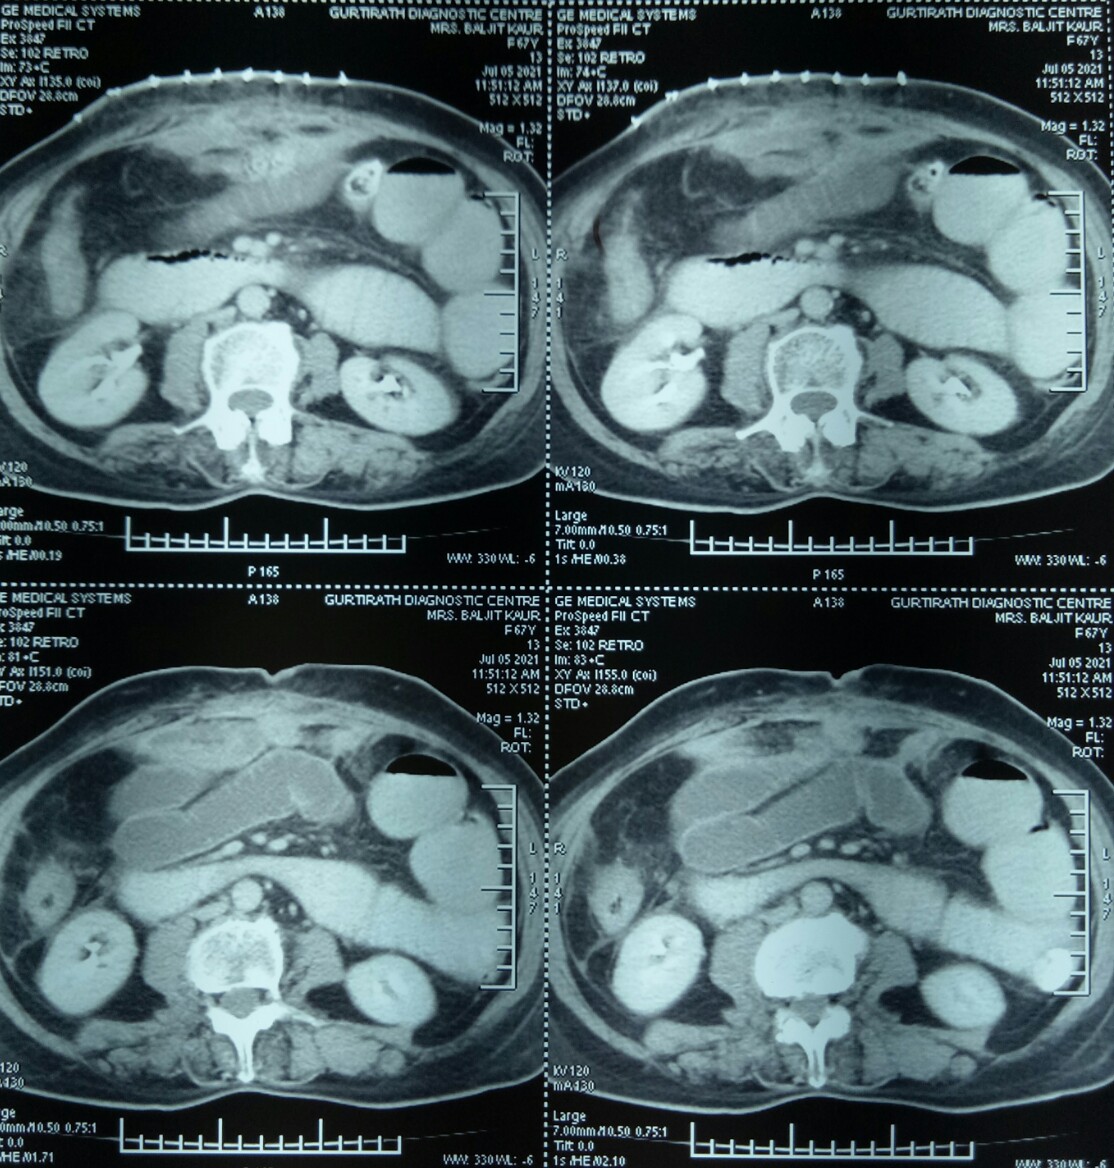

An incisional hernia (that had recurred perhaps for the third time) in the right upper part of the abdomen repaired in a 65 years old female. Because of the history of multiple operations earlier, a CT scan was performed and showed a defect in the anterior abdominal wall with a loop of intestine protruding.

CT scans confirmed grossly dilated small bowel loops in the pelvis and left flank and one jejunal loop high in the centre, besides showing a mass of dense adhesions just under the staple line of the hernia surgery.